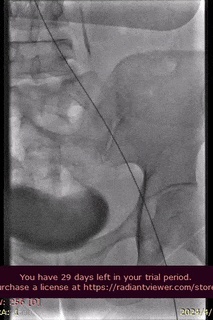

病例分享

山西省人民医院使用分享。

手术过程